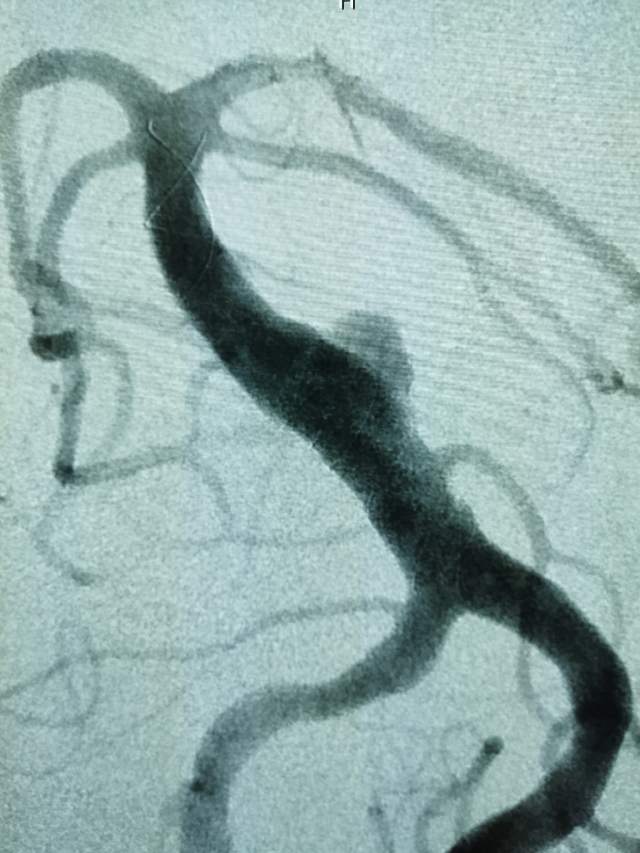

椎基底动脉冗长扩张症,是最棘手最复杂的脑血管病之一。患者从外地千里迢迢(3900余公里,仅高铁41小时)赶来东方医院诊治,期间症状不断加重(图2非真实大小)。术后一周复查:1、右侧肢体肌力明显改善;2、右侧肢体和枕部麻木症状明显改善;3、饮水呛咳缓解;4、共济失调明显改善;5、流涎消失;6、消失的味觉再次恢复。术后一周复查:血管修复良好(图5)。期待患者早日康复,早日奔赴工作岗位,保一方平安。